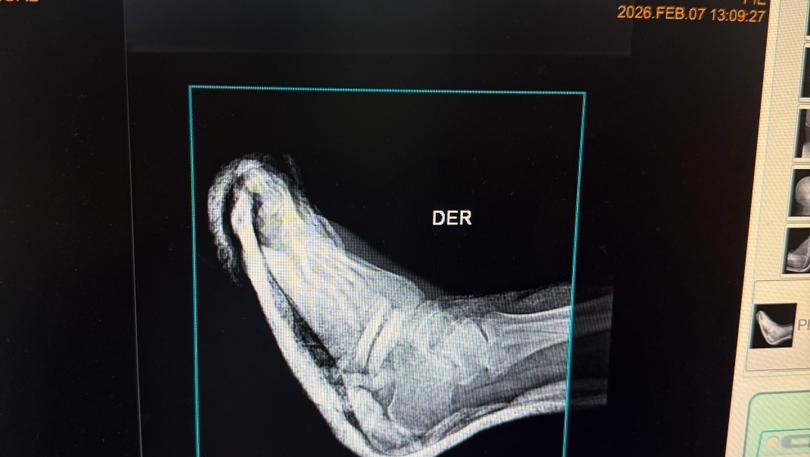

A sus 27 años, Jean Manuel Colella estaba cumpliendo una de sus metas más grandes: realizar sus prácticas universitarias en Barquisimeto, Venezuela. Sin embargo, la madrugada del 07 de febrero, su vida cambió en un segundo. Fue víctima de un terrible accidente automovilístico donde, lamentablemente, los responsables se dieron a la fuga, dejándolo atrás con heridas graves. Hoy, Jean Manuel enfrenta el reto más difícil de su vida. El accidente le causó múltiples fracturas en ambas piernas, siendo su pie derecho el más afectado. Para que él pueda volver a caminar, trabajar y terminar su carrera, necesita una cirugía de reconstrucción urgente. Cada granito de arena cuenta. Tu donación, por pequeña que parezca, es un paso más cerca de devolverle la movilidad a un joven que tiene todo un futuro por delante. ¡Ayúdanos a que Jean Manuel vuelva a ponerse de pie!

At the age of 27, Jean Manuel Colella was achieving one of his biggest goals: completing his university internship in Barquisimeto, Venezuela. However, in the early hours of February 7th, his life changed in an instant. He was the victim of a horrific car accident where, heartlessly, those responsible fled the scene, leaving him behind with severe injuries. Today, Jean Manuel faces the toughest challenge of his life. The accident caused multiple fractures in both legs, with his right foot being the most severely affected. In order for him to walk again, work, and finish his degree, he needs urgent reconstructive surgery. Every little bit helps. Your donation, no matter how small it may seem, is one step closer to restoring mobility to a young man with his whole future ahead of him. Help us get Jean Manuel back on his feet!